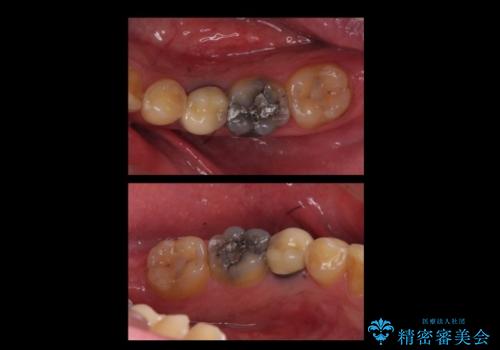

インプラントの向かい合わせの歯や隣の歯の虫歯治療も併せて行なっています。

同時期に治療することで咬み合わせの調整がしやすく、また、適合の良いものを作成できるメリットがあります。

左上7・左下7:PGAインレー 各6万円